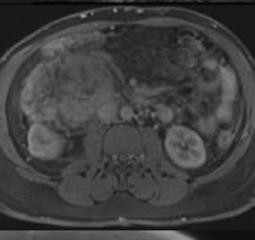

Creative Director

Tim Uden

Design Manager

Stacey White

Senior Designers

Owen Silcox

Tamara Kondolomo

Creative Artworker

Dillon Benn Grove

Designers

Shanjok Gurung, Fabio van Paris

Junior Designer

Helena Spicer